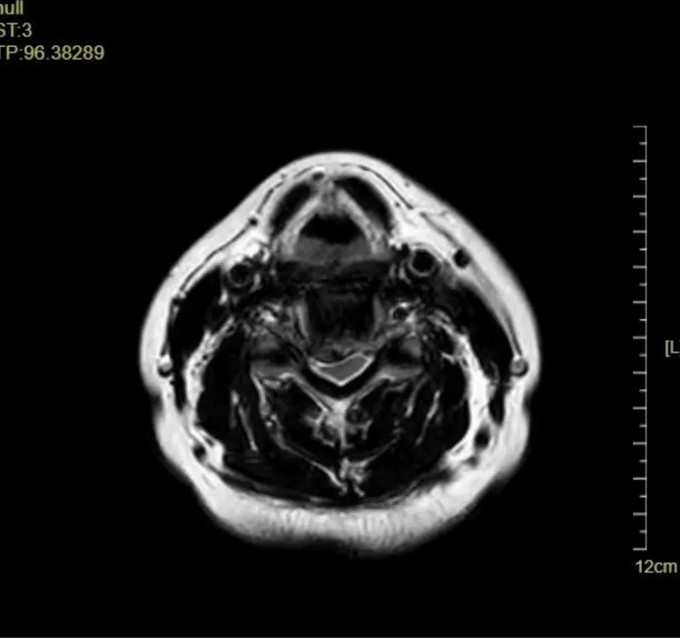

頸椎MRI橫斷位

C4-5、C5-6椎間盤突出伴鈣化,C4-5、C5-6 層面脊髓變性。